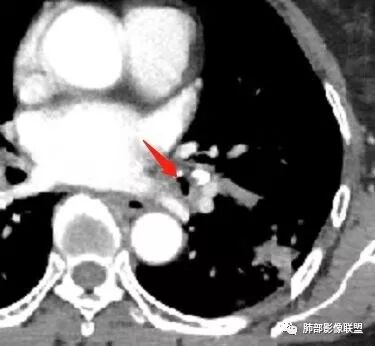

这三幅图是连续的,我们看到支气管中间这一幅狭窄了

大——小——大,狭窄后扩张

从这幅图看好像与周围病灶分界不清,支气管腔狭窄后扩张,支持炎性